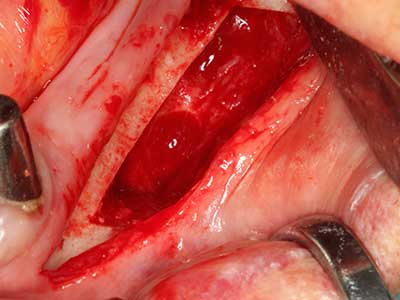

Пиезохирургията има допълнителни предимства при събиране на костни блокове. В допълнение към високата прецизност при остеотомията, описана по-горе, употребата на фините режещи накрайници значително намаляват загубата на материал. Голяма загуба на материал по време на събиране може да се очаква с дебелите накрайници, особено при употреба на борери Линдеман (Lakshmiganthan, Gokulanathan et al. 2012). Базалното разделяне, което е необходимо, особено за присадка на блок при ретромолар, е улеснено от специално създадени правоъгълни триони. В резултат на това, пиезохирургията е разглеждана като прецизна, улеснена и безопасна процедура за събиране на костни блокове в ретромоларното пространство (Happe 2007) (Фиг. 1-12).